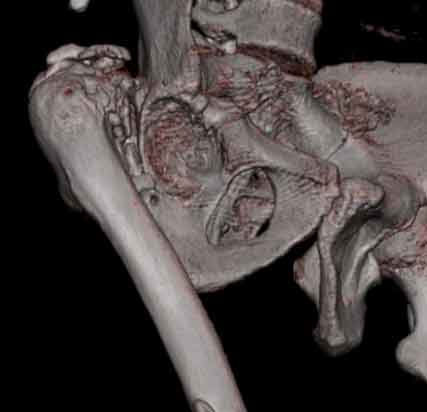

Уважаемые коллеги, пациент 30 лет, 4 года назад попал под поезд, ампутация обеих голеней в в/3, подвздошный вывих бедра (теперь застарелый). несмотря на такую ситуацию, пациент вполне прилично ходит и объем движений в неоартрозе близок к неповрежденной стороне. Основная жалоба - боль при нагрузке и в покое. Планируем двухэтапное лечение: резекция шейки, мобилизация проксимального отдела бедра, низведение бедра АВФ, вторым этапом б/ц эндопротезирование. Как поступить с головкой, вроде бы при протезировании можно будет обойтись без пластики, или ошибаюсь? Оставить ее там, где она есть? Другие варианты лечения.